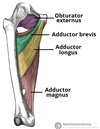

What is this muscle?

What is this muscle?